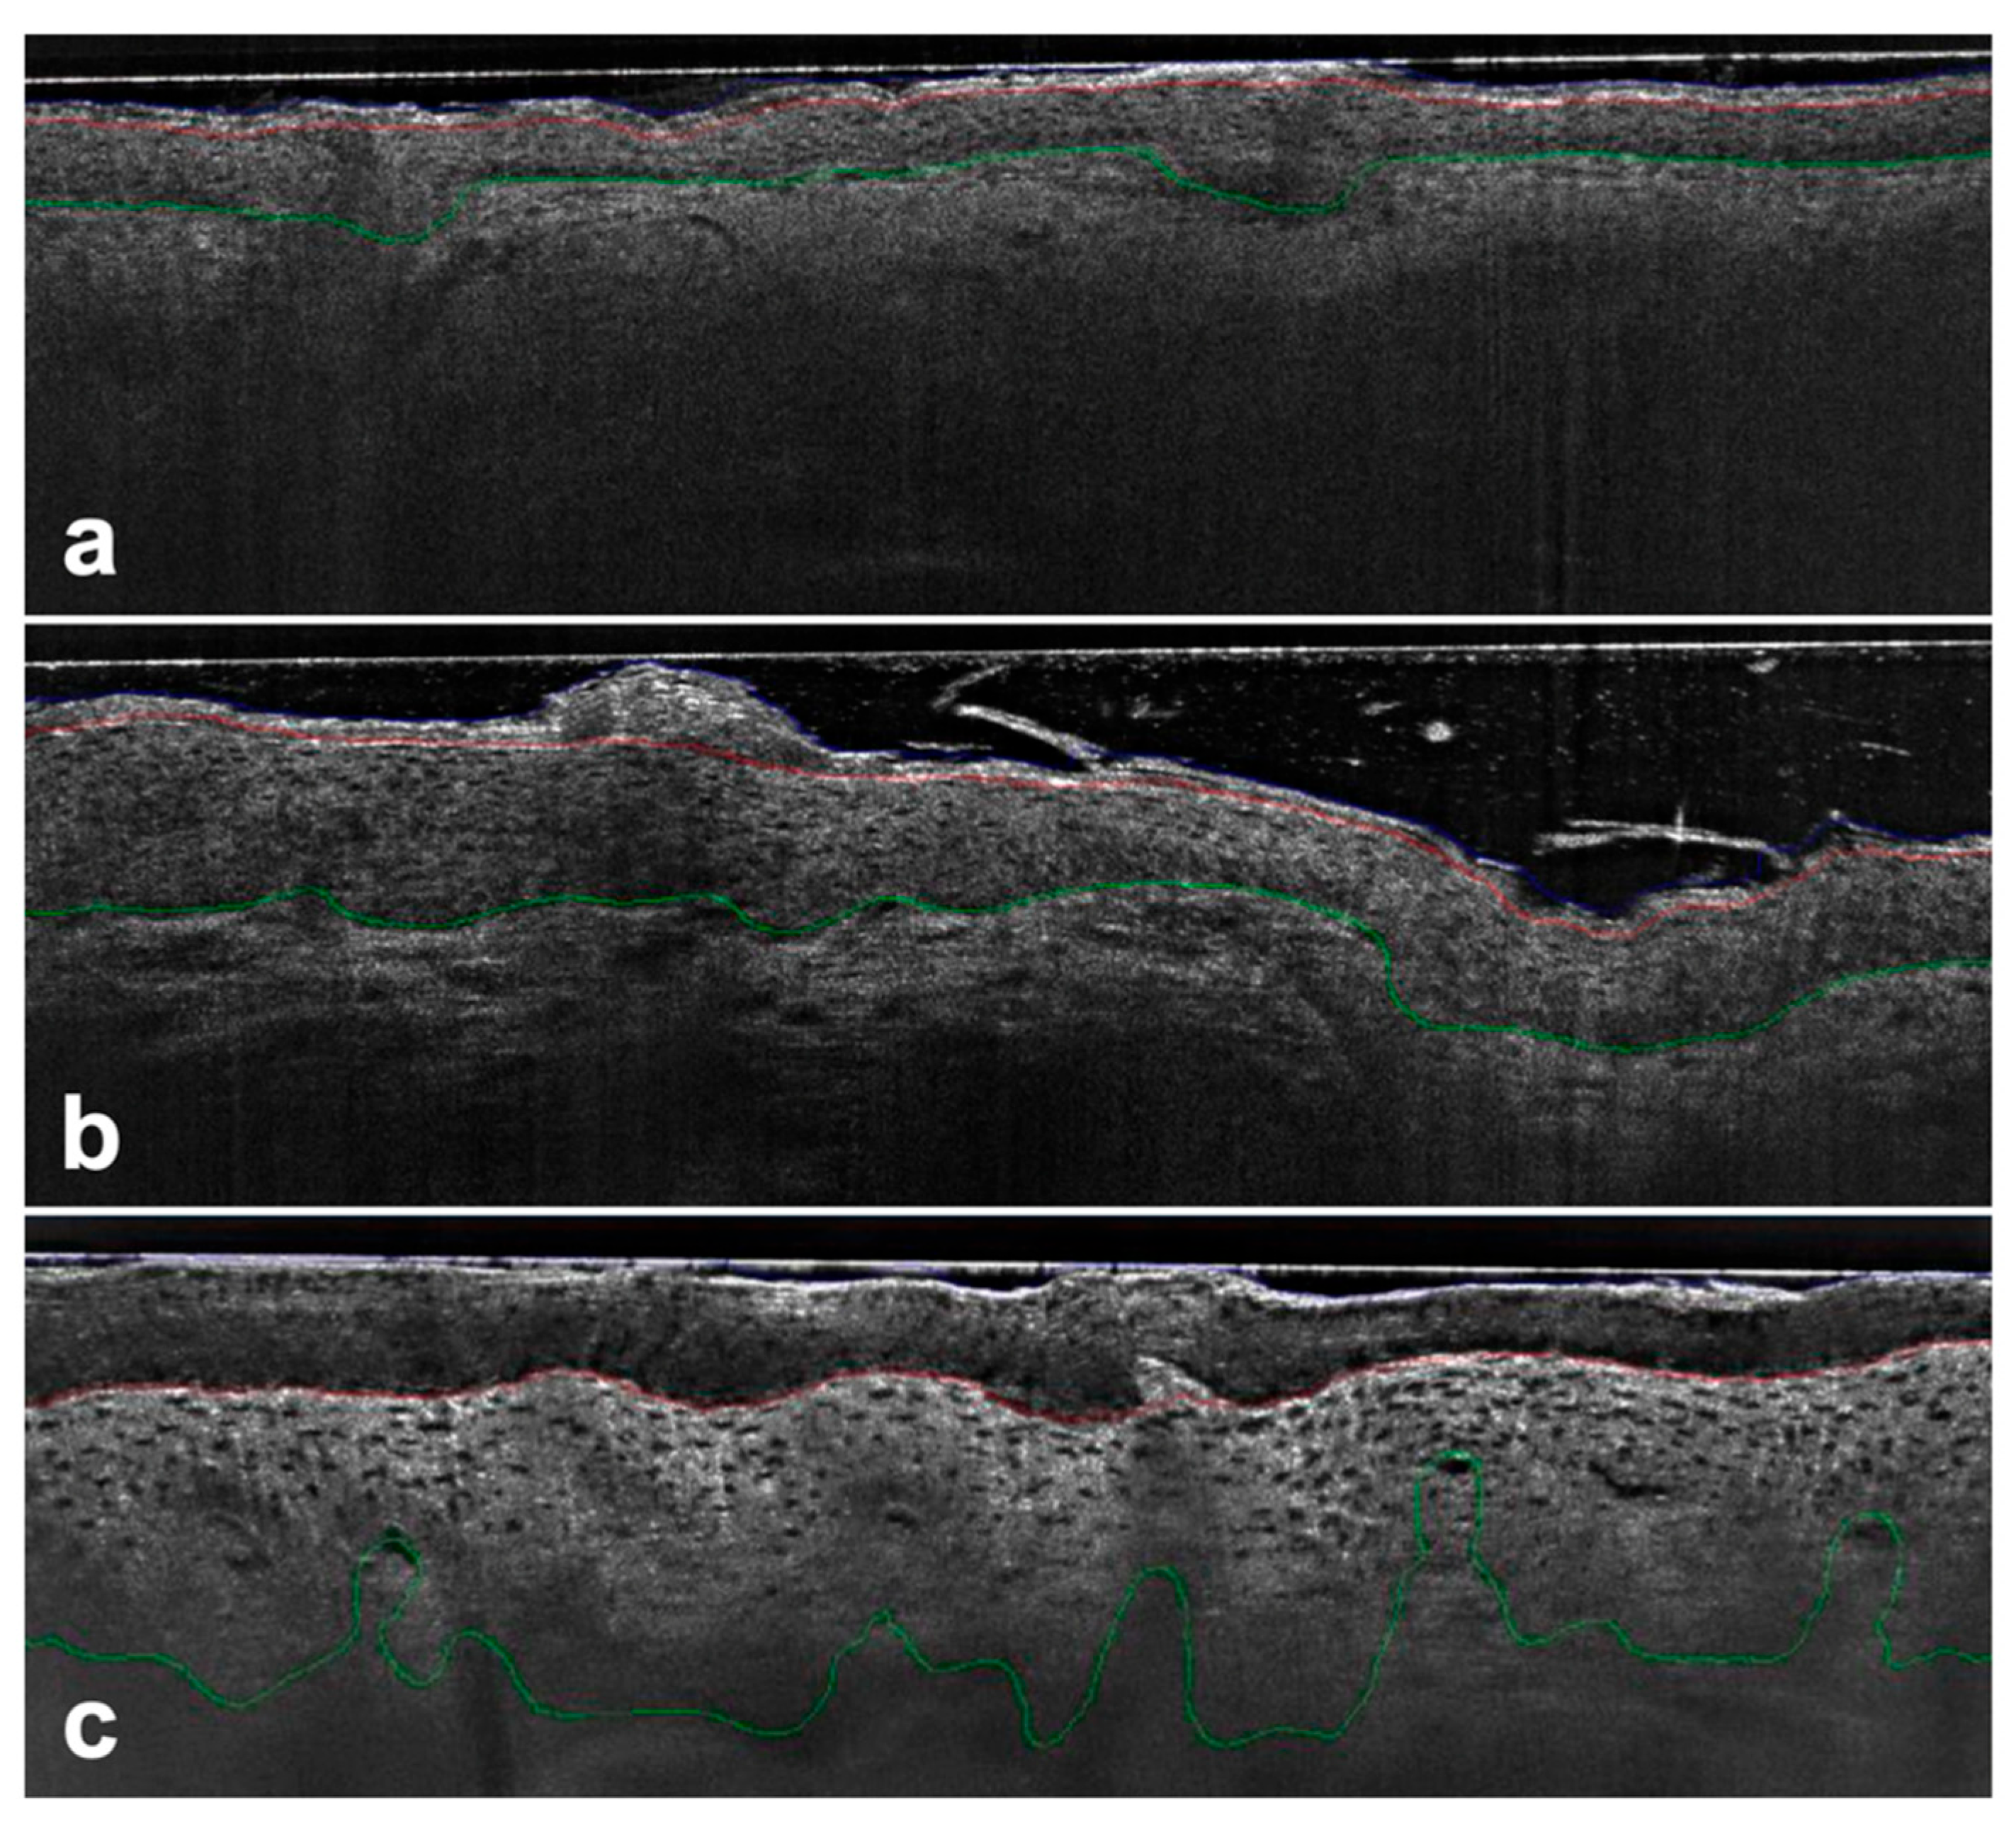

Figure 1. AK PRO score assessment in vertical LC-OCT images (DeepLive, DAMAE Medical, Paris, France) image size: 1.2 × 0.5 mm2, lateral and axial resolution: 1.1 μm × 1.3 μm—Protrusions were detected by comparing the position of the DEJ (green line) to a reference estimator in the upper epidermis (red line) with no protrusions detected using the algorithm for PRO I (a), while for PRO II (b) and PRO III (c) the basal epidermis protruded progressively into the dermis.

Protrusions were detected by comparing the position of the DEJ with a reference estimate of the flat DEJ position. The skin surface was used as an estimate offset by the average thickness of the epidermis. Areas with DEJ below the estimated value were classified as protrusions. Once these regions were identified, the ledge width was quantified as the distance between two intersections where DEJ crossed the estimator.

To address this limitation and considering that the interaction between the epidermis and dermis, along with tumor invasiveness, originates at the dermoepidermal junction zone, a histomorphological classification based on the basal growth pattern (PRO I–III) of atypical keratinocytes has been proposed [9]. The PRO score is a widely used clinical scoring system for AK-based histological findings at the DEJ [10]. While early-stage PRO I is characterized by clustered and atypical keratinocytes in basal epidermal layers, PRO II shows how small hemispherical buds from the basal epidermis slightly protrude into the upper papillary dermis. In PRO III, we can see spiky or filiform papillary elongations of atypical keratinocytes protrude into the upper dermis [10,11].